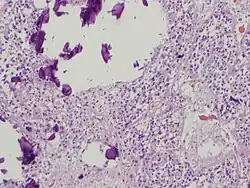

Men spreekt van calcificatie of verkalking, wanneer kalkzouten zich afzetten in levend of dood weefsel. In de geneeskunde spelen verkalkingen in vele organen een rol, zoals de aders, de pijnappelklier en de borst.

Verkalking kan in organismen optreden in littekenweefsel, in gedegenereerd weefsel (dystrofe calcificatie) en in alle weefsels door een te hoog kalkgehalte in het bloed (metastatische calcificatie). Kalk kan zich in plaques afzetten.